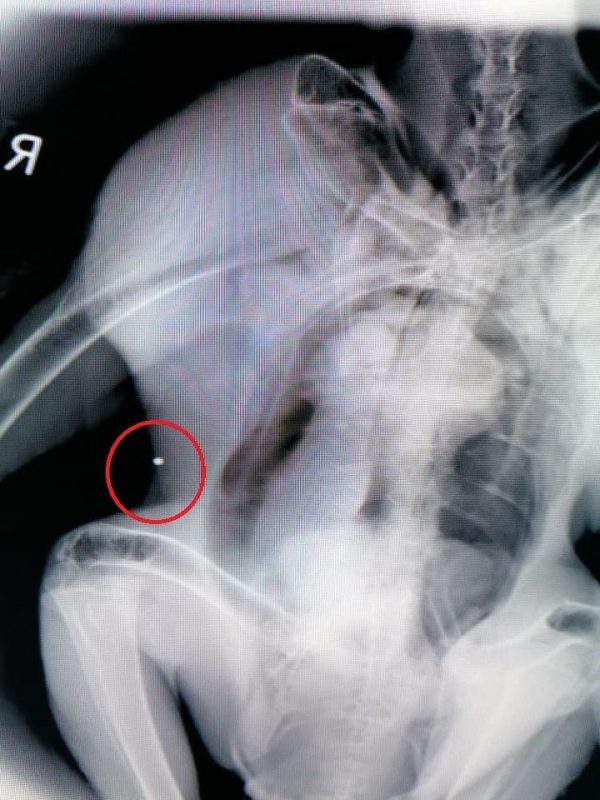

Πολλά χρόνια είχαμε να δούμε σκάγια σε ακτινογραφία γύπα. Νεαρό όρνιο έφτασε χτες από Χανιά, με αποστολέα το Δασαρχείο Χανίων κι ένα σοβαρό κάταγμα στη φτερούγα. Στην ακτινογραφία βρήκαμε σκάγι, αλλά δεν είμαστε σίγουροι ακόμη ότι το κάταγμα οφείλεται στον πυροβολισμό, ο οποίος ενδέχεται να είναι προγενέστερος. Σε κάθε περίπτωση πρόκειται για λαθροθηρία και μάλιστα σε αυστηρά προστατευόμενο είδος.